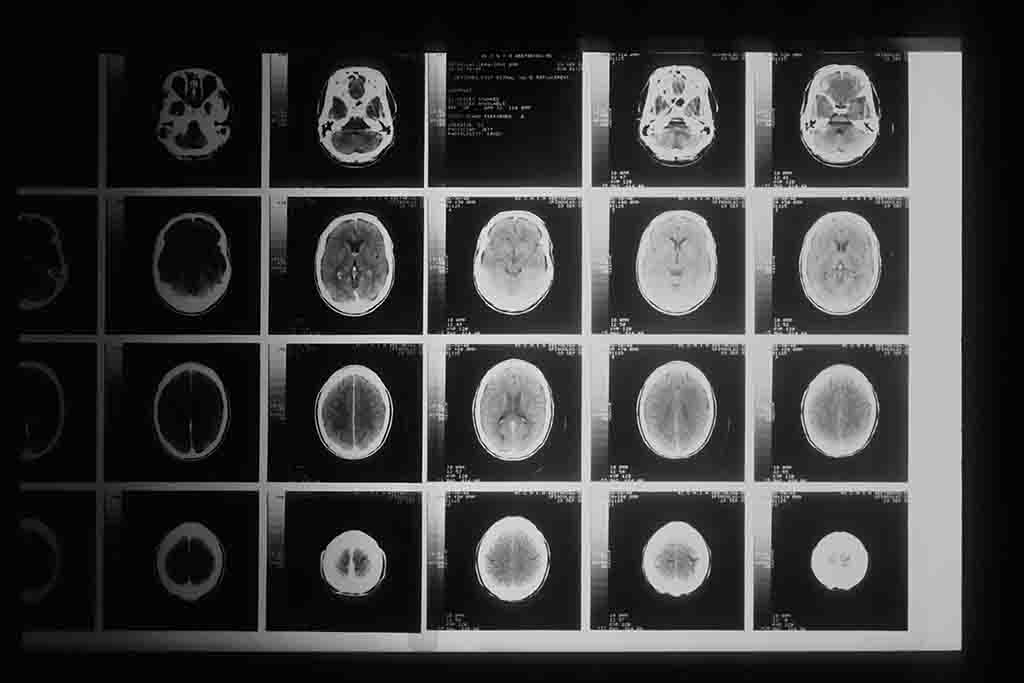

2. 방사선 전문의 및 의료 영상 진단 분야

X-ray, MRI, CT 등 의료 영상 분석에서 AI는 보조 도구로 널리 활용되고 있다.

특히 미세한 이상 징후 탐지나 1차 스크리닝에서는 AI가 빠르고 일관된 성능을 보인다.

의사는 AI 분석 결과를 기반으로 최종 판단과 치료 결정을 내리는 구조로 변화 중이다.